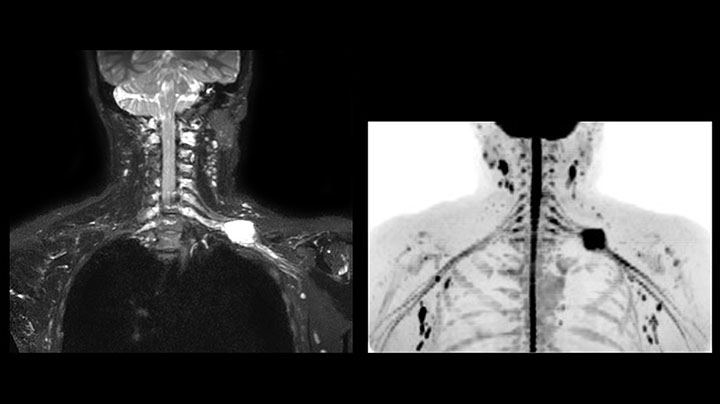

MRI of Pancoast tumor

Although the area between the neck and the top of the lung is one of the most difficult areas for MRI, Prodiva 1.5T images show good quality in this 56-year-old male with Pancoast tumor on the right. mDIXON TFE images shows excellent fat suppression in the neck area and the DWI shows almost no distortion.